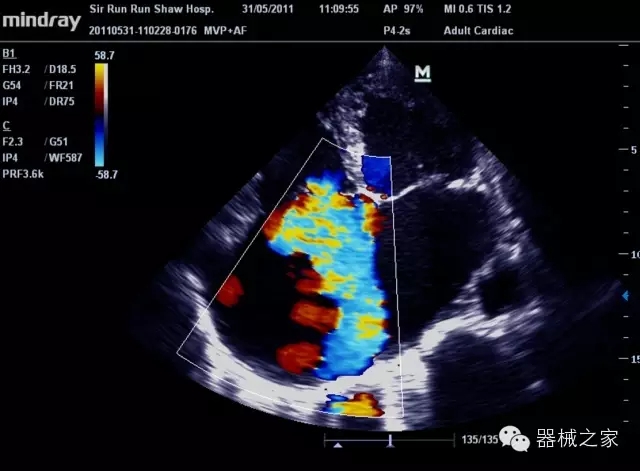

臨床圖片賞析

產(chǎn)品特點(diǎn)

8倍波束并行處理系統(tǒng)

·在便攜式緊湊平臺(tái)上采用更多倍波束并行接收信號(hào)處理模式,無(wú)論二維還是彩色血流圖像狀態(tài)下,擁有更靈敏的回波頻移捕獲能力,大大提高時(shí)間分辨率,尤其使得心血管表現(xiàn)更為突出;